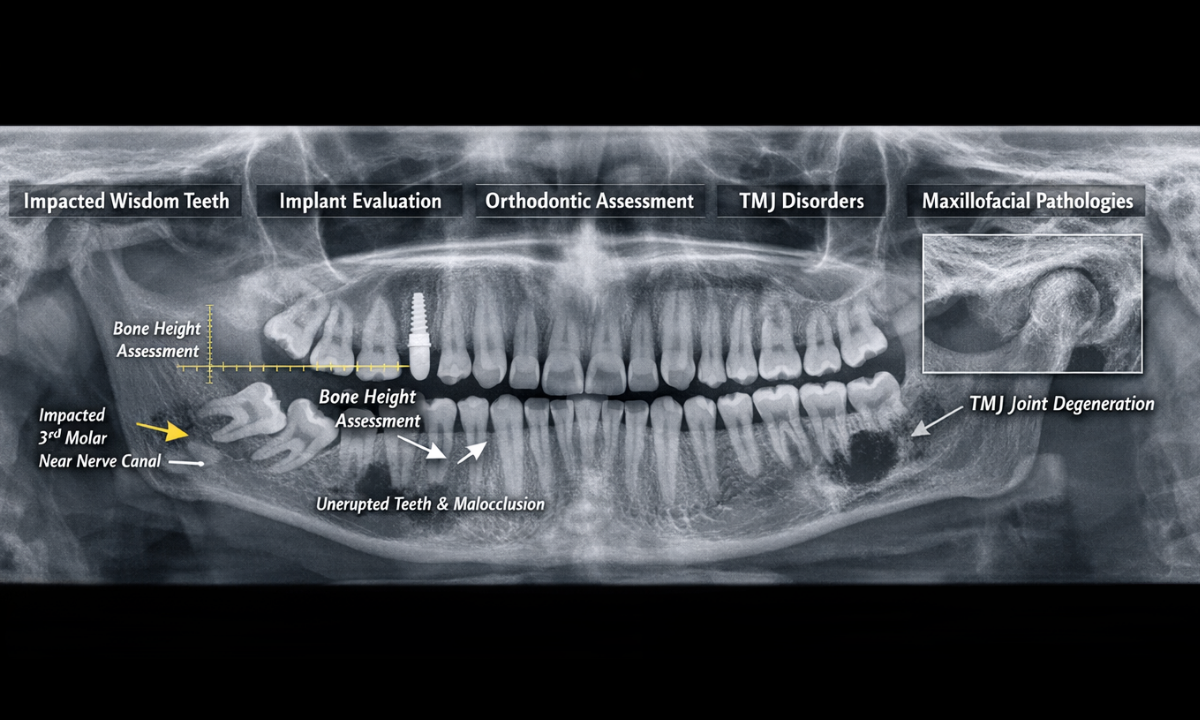

2. The Diagnostic Imperative: Outlining the specific maxillofacial pathologies, such as impacted third molars, hidden osseous cysts, and severe temporomandibular joint degradation, that strictly require panoramic evaluation before any surgical intervention.

| Impacted Third Molars (Wisdom Teeth) | Mandibular angle and the inferior alveolar nerve canal. | To precisely determine the angle of tooth impaction and accurately measure the exact distance between the tooth roots and the primary mandibular nerve before complex surgical extraction. |

| Comprehensive Implant Planning | Maxillary and mandibular alveolar bone ridges. | To evaluate vertical bone height, assess overall bone density, and map the precise location of the maxillary sinuses to strictly ensure anatomical viability for titanium implant placement. |

| Advanced Orthodontic Assessment | The complete dental arch and all unerupted developing dentition. | To evaluate severe malocclusion, track the specific eruption pathways of permanent teeth in pediatric patients, and formulate precise, long-term structural alignment strategies. |

| Temporomandibular Joint (TMJ) Disorders | The temporomandibular joint condyles and the articular fossa. | To definitively detect gross structural asymmetry, advanced condylar degradation, or severe arthritic changes contributing to chronic jaw dysfunction and facial pain. |

| Hidden Maxillofacial Pathologies | Deep osseous tissues of the upper and lower jawbones. | To safely identify asymptomatic, deep-seated bone cysts, aggressive odontogenic tumors, or severe periodontal bone resorption that standard localized X-rays cannot capture. |